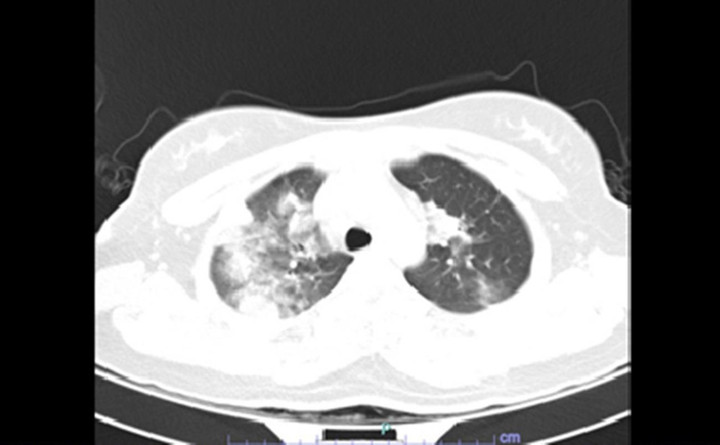

Hình ảnh chụp CT ngực của bệnh nhân khi nhập viện. (Ảnh: BVCC).

Kết quả xét nghiệm máu cho thấy nhiễm trùng tăng cao, giảm oxy hoá máu nặng. Kết quả cắt lớp vi tính lồng ngực có hình đông đặc phổi, nhiều tổn thương nốt, kính mờ viêm rải rác.